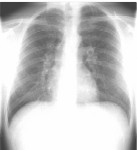

Συγκρίνετε το αποτέλεσμα ρύθμισης φωτεινότητας και ρύθμισης φωτεινότητας πολλαπλών κλιμάκων σε μια εικόνα θώρακα CR:

Μια εικόνα με αυξημένη αντίθεση που χρησιμοποιεί ρύθμιση φωτεινότητας εμφανίζει αποκοπή